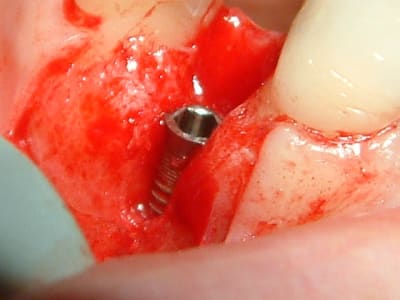

ce matin, j'ai essayé le cerasorb avec une membrane Tefgen... qui a une expérience de ces matériaux?

voici les clichés et j'ai hâte de voir ce que çà va donner..

@+

(oups, ouvrir dans l'ordre cliché 31, 32 etc...)

mes clichés sont pris par moi même avec un fuji finepix 7000 en mode super macro et lumière du scialytique (et avec la résolution la plus basse que propose cet appareil)

pour la stérilité je troue le côté papier d'une gaine pour laisser passer l'objectif puis je stérilise cette gaine à l'autoclave. ci joint un cliché du dispositif.

c'est simple et efficace (le côté transparent de la gaine me laisse visualiser l'image sur l'ecran du viseur)